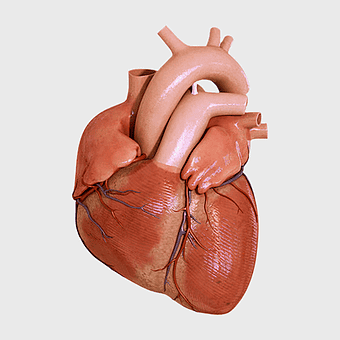

Heart Anatomy Diagram, human heart drawing, realistic heart illustration, cardiovascular system, medical illustration, organ structure, human anatomy study -

human heart anatomy, cardiovascular system illustration, medical heart diagram, heart organ structure, human body organ visuals, anatomical heart drawing, heart health -

human heart diagram, cardiovascular system anatomy, blood vessel chart, free body diagram, circulatory system illustration, medical organ visualization, human anatomy study -

human heart anatomy, cardiac muscle illustration, circulatory system model, heart health visual, cardiovascular organ diagram, medical heart image, visceral structure depiction -

human heart anatomy, red heart illustration, heart organ diagram, heart muscles and valves, cardiovascular system diagram, human body organ chart, anatomical heart structure -

human heart anatomy, superior vena cava illustration, systemic circulation diagram, heart rate visual, cardiovascular system study, medical organ depiction, human body organ reference -

heart anatomy diagram, human heart ventricle, human body physiology, heart beat animation, cardiovascular system, medical illustration, organ structure analysis -

human heart illustration, cardiac anatomy diagram, heart blood vessels, medical organ visuals, cardiovascular system chart, human anatomy study, circulatory system illustration -

human heart anatomy illustration, watercolor heart painting, heart shape medical care, red heart organ, cardiovascular system diagram, anatomical heart drawing, heart structure analysis -

human heart anatomy, heart science illustration, human body heart diagram, cardiovascular system, cardiac structure, medical heart image, heart health education -

heart anatomy illustration, cardiovascular system diagram, circulatory system medical, vascular system sonography, human body blood flow, arterial network visualization, heart function analysis -

heart anatomy diagram, circulatory system illustration, superior vena cava label, inferior vena cava structure, cardiovascular system chart, human heart ventricles, medical education graphics -